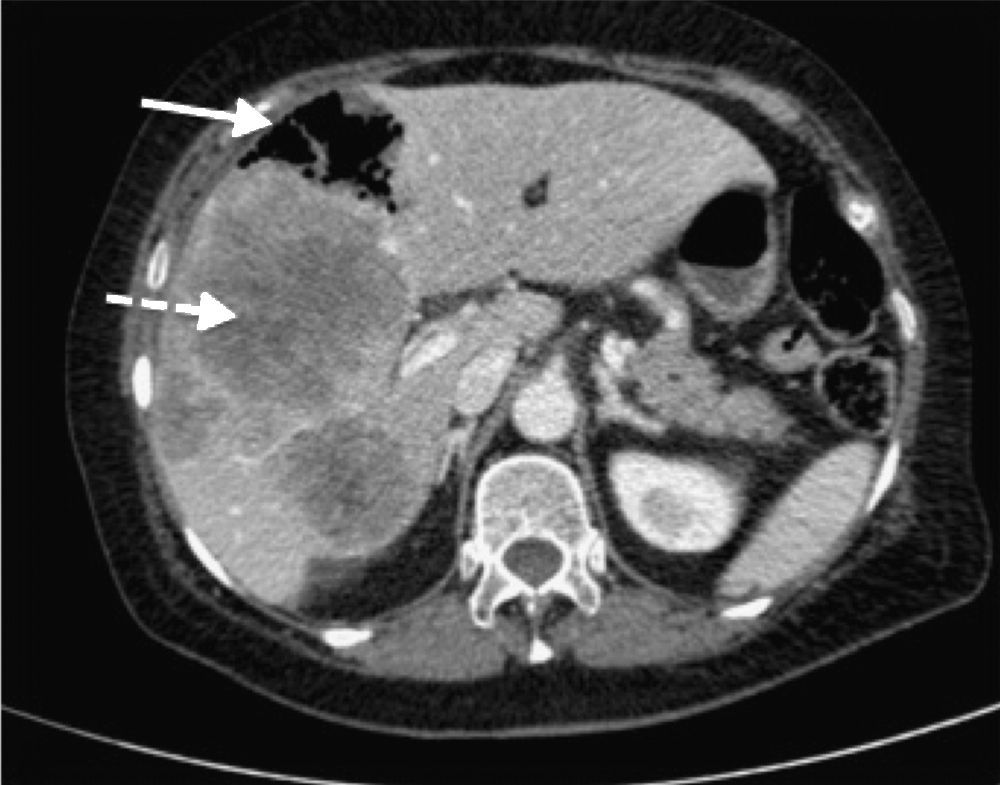

Based on this image's title: “Multidrug resistant citrobacter: an unusual cause of liver abscess ...”